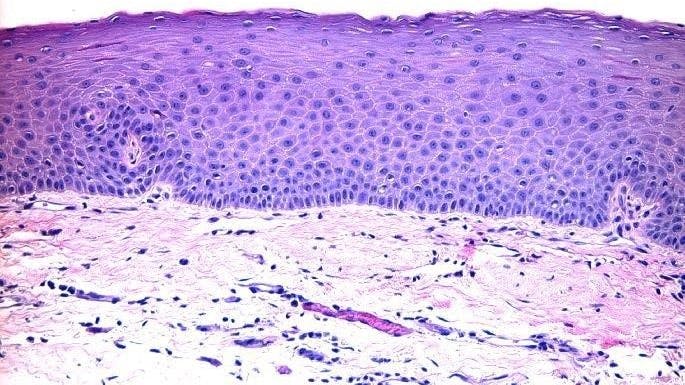

A pathology report was ordered, a deep-shave biopsy was performed, and the nodule removed. Pathology showed the mucus membrane with compressed fibrous tissue within the lamina proper and associated sparse inflammation (figures 3 and 4).

This report describes a lesion of the lower attached gingiva that was definitively diagnosed by histologic examination as a mucocele or mucous retention cyst. The usual location of mucoceles is on the lower lip. However, this case illustrates an uncommon presentation of a mucocele with respect to location.

Mucoceles are benign lesions that are filled with mucus and can appear in the mouth, appendix, paranasal sinuses, lacrimal sac, appendix, or gall bladder.1 Generally, mucoceles occur as a sphere and are asymptomatic. Mucocele is the seventeenth most common salivary gland lesion found in the oral cavity. The clinical appearance is typically a distinct, fluctuant, painless, bluish swelling of the mucosa. Most lesions are smaller than 1 cm in diameter. They form due to mucus accumulating when there is an alteration in the minor salivary gland that leads to limited swelling. Mucoceles typically do not form on the attached gingiva.